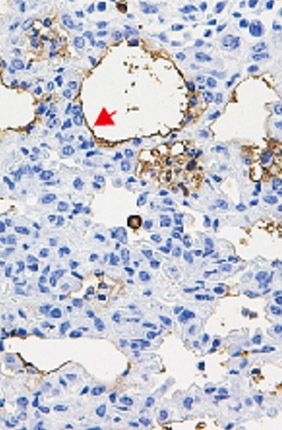

MME will also address the effect of environmental pollutants on humans. Microbes carry out biotransformations on foreign substances that enter the body–toxic substances can be made non-toxic, but the reverse is also true. The researchers will look at these processes in the gut and the lung to understand how environmental toxicants affect human/microbiome interactions, the impact on the host, and how to alleviate any harm they cause.